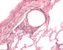

Präparat 70: Lunge, Blutgefäße, Darstellung durch Injektion von Tusche, Gegenfärbung mit Kernechtrot

In diesem Präparat wurde das Gefäßsystem der Lunge dargestellt durch Injektion von Tusche in die großen Gefäße. Das Lungenparenchym wurde durch Gegenfärbung mit Kernechtrot sichtbar gemacht. Zu erkennen sind tuschegefüllte Lungenvenen, Vv. pulmonales (einzeln im Parenchym verlaufend), Lungenarterien, Aa. pulmonales (in der Nachbarschaft der Bronchi und Bronchioli) und die Kapillaren in Interalveolarsepten.